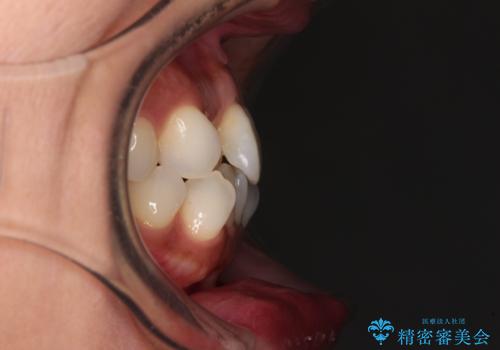

前歯のクロスバイト インビザラインによる矯正治療

- 上下のクロスバイトと前歯のデコボコを気にして来院された患者様です。

インビザライン特有の、治療後半に奥歯が咬み合わないという事象が長引きました。

咬み合わないときの対処方法は色々とありますが、ゴムかけなどを活用して噛めるようにしました。